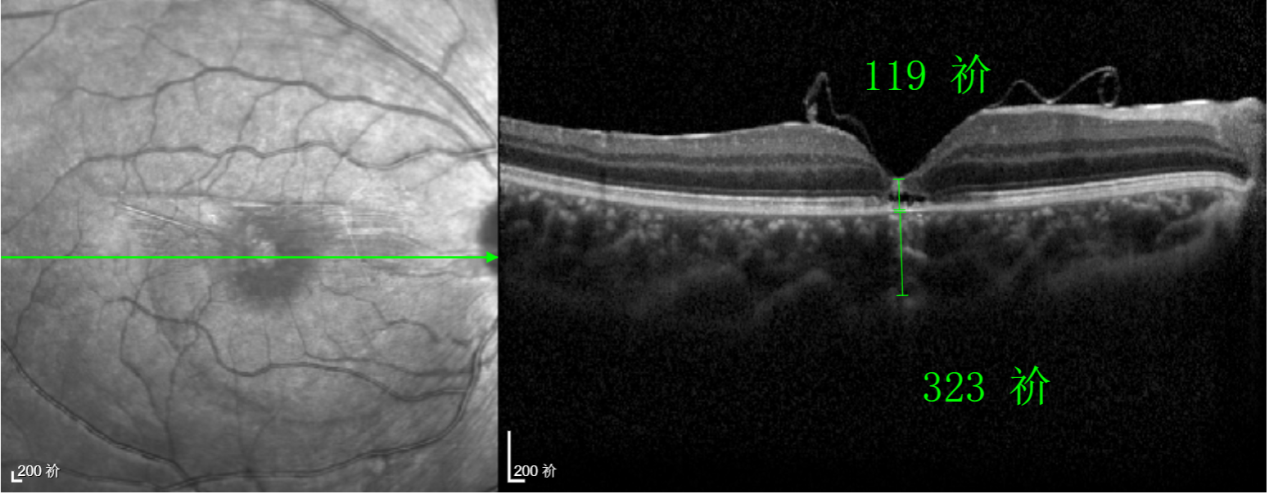

除此之外,利用自體組織覆蓋為黃斑裂孔提供了理想的愈合環(huán)境,裂孔閉合速度顯著快于傳統(tǒng)方法。誠誠接受手術(shù)24小時(shí)后,檢查可見內(nèi)界膜瓣位置良好;術(shù)后1個(gè)月,黃斑裂孔已經(jīng)閉合,視力恢復(fù)到0.5;術(shù)后兩個(gè)月,視力進(jìn)一步提升到0.7。

“書本的文字都變直了,黑板上的字也更清晰了!”

術(shù)后3個(gè)月復(fù)查時(shí),小男孩的眼睛閃耀著自信的光芒。